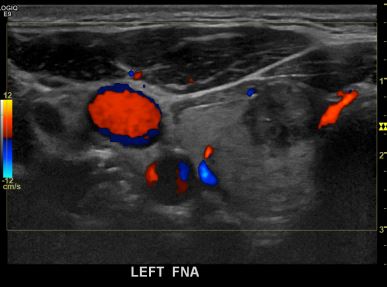

상기환자  외부검사이상소견으로 내원하신 30대 후반 남성분으로 의심스러운 갑상선 좌엽혹 세포검사진행후 갑상선암으로 진단되었습니다